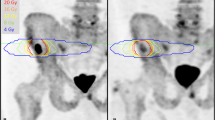

The same five target lesions identified on WB-MRI were delineated as VOIs on the respective baseline 18F-NaF and 18F-choline PET images using HERMES Gold software (Hermes Medical Solutions, Inc.) (Fig. 2). For each metastasis, the SUVmax was recorded. For per-patient analyses, the average value across all targets was calculated.

Target lesion measurements in a 65-year-old metastatic castrate-resistant prostate cancer patient, 5 target lesions on b900 DWI, ADC (with green segmentation), T1-weighted and 18F-NaF PET/CT fusion, and PET (delineated) images; apparent difference in lesion size between DWI and PET images may relate to the difference in functional properties used to generate image contrast, variance in patient positioning, and slice selection as well as difference in resolution of these two imaging techniques